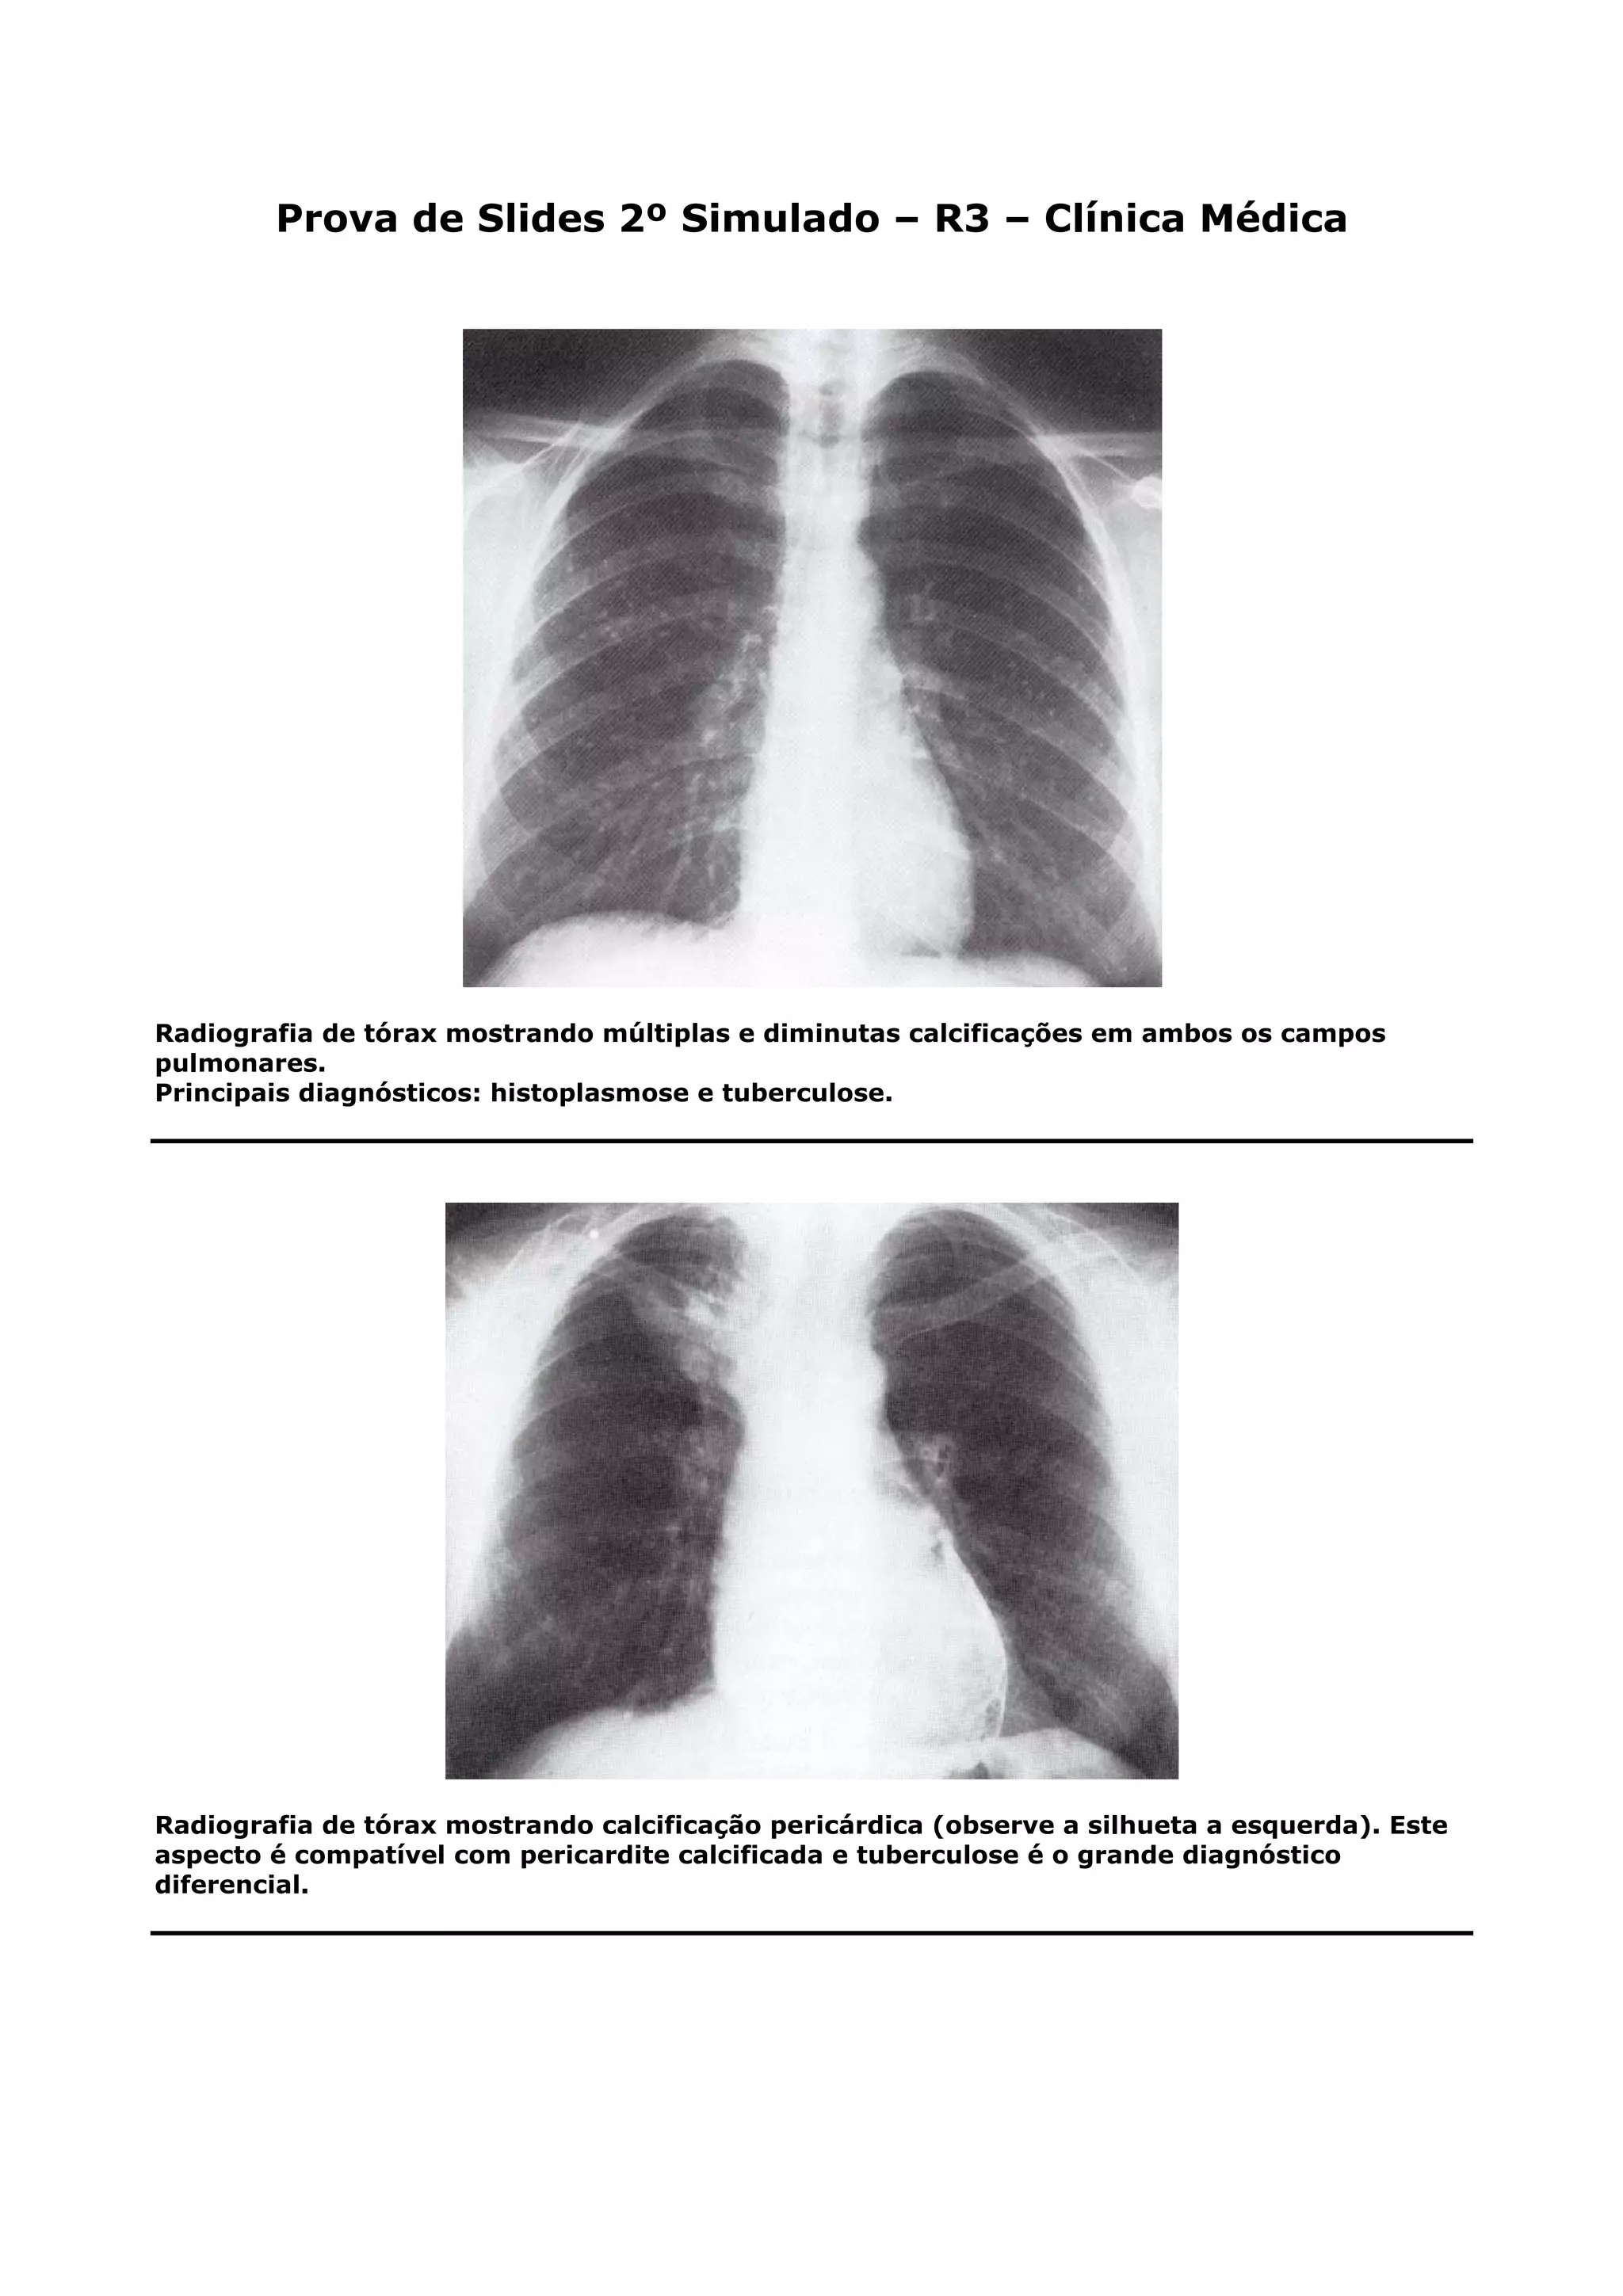

Radiografia de tórax mostrando múltiplas e diminutas calcificações em ambos os campos

pulmonares.

Principais diagnósticos: histoplasmose e tuberculose.